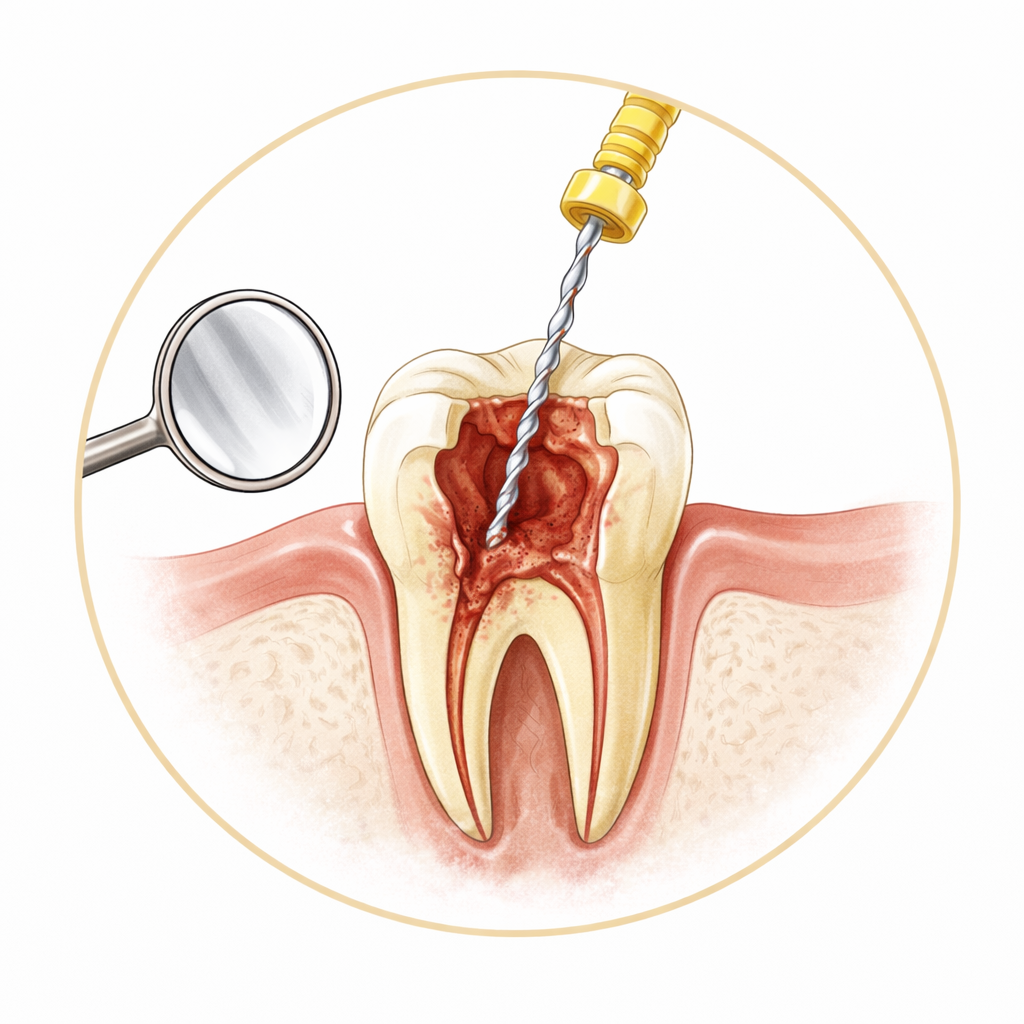

Dolgu, kanal tedavisi, diş çekimi, diş eti tedavisi ve koruyucu bakım — günlük diş sağlığınız için.

Tedaviler